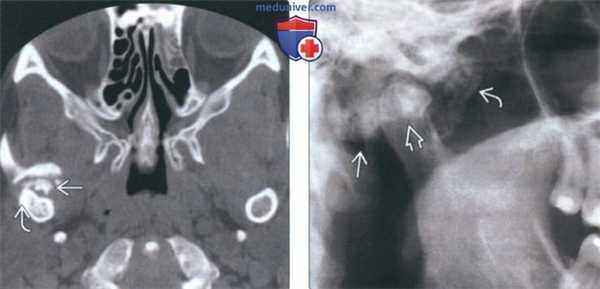

(Слева) На аксиальной КТ правого ВНЧС в коаном окне спереди ог мыщелка визуализируются «грубые» обызвеавления. Кортикальная пластинка мыщелка интактна, наружный полюс склерозирован вследавие дегенеративных изменений.

(Справа) На панорамном изображении правого ВНЧС визуализируется мыщелок обычных размеров и формы. Спереди и сзади от мыщелка определяется неоднородное затемнение. Объемное образование имеет большие размеры и приводит к рааяжению суаавной капсулы.

3. КТ при первичном синовиальном хондроматозе ВНЧС:

• КТ в костном окне:

о Множественные обызвествленные/оссифицированные узлы вокруг мыщелка нижней челюсти

о Часто обнаруживаются дегенеративные изменения суставной поверхности мыщелка:

- Неровный контур, склероз

о Расширение суставного пространства

о Может обнаруживаться отек мягких тканей или объемное образование смешанной плотности, солидная часть которого отражает метаплазию синовиальной ткани